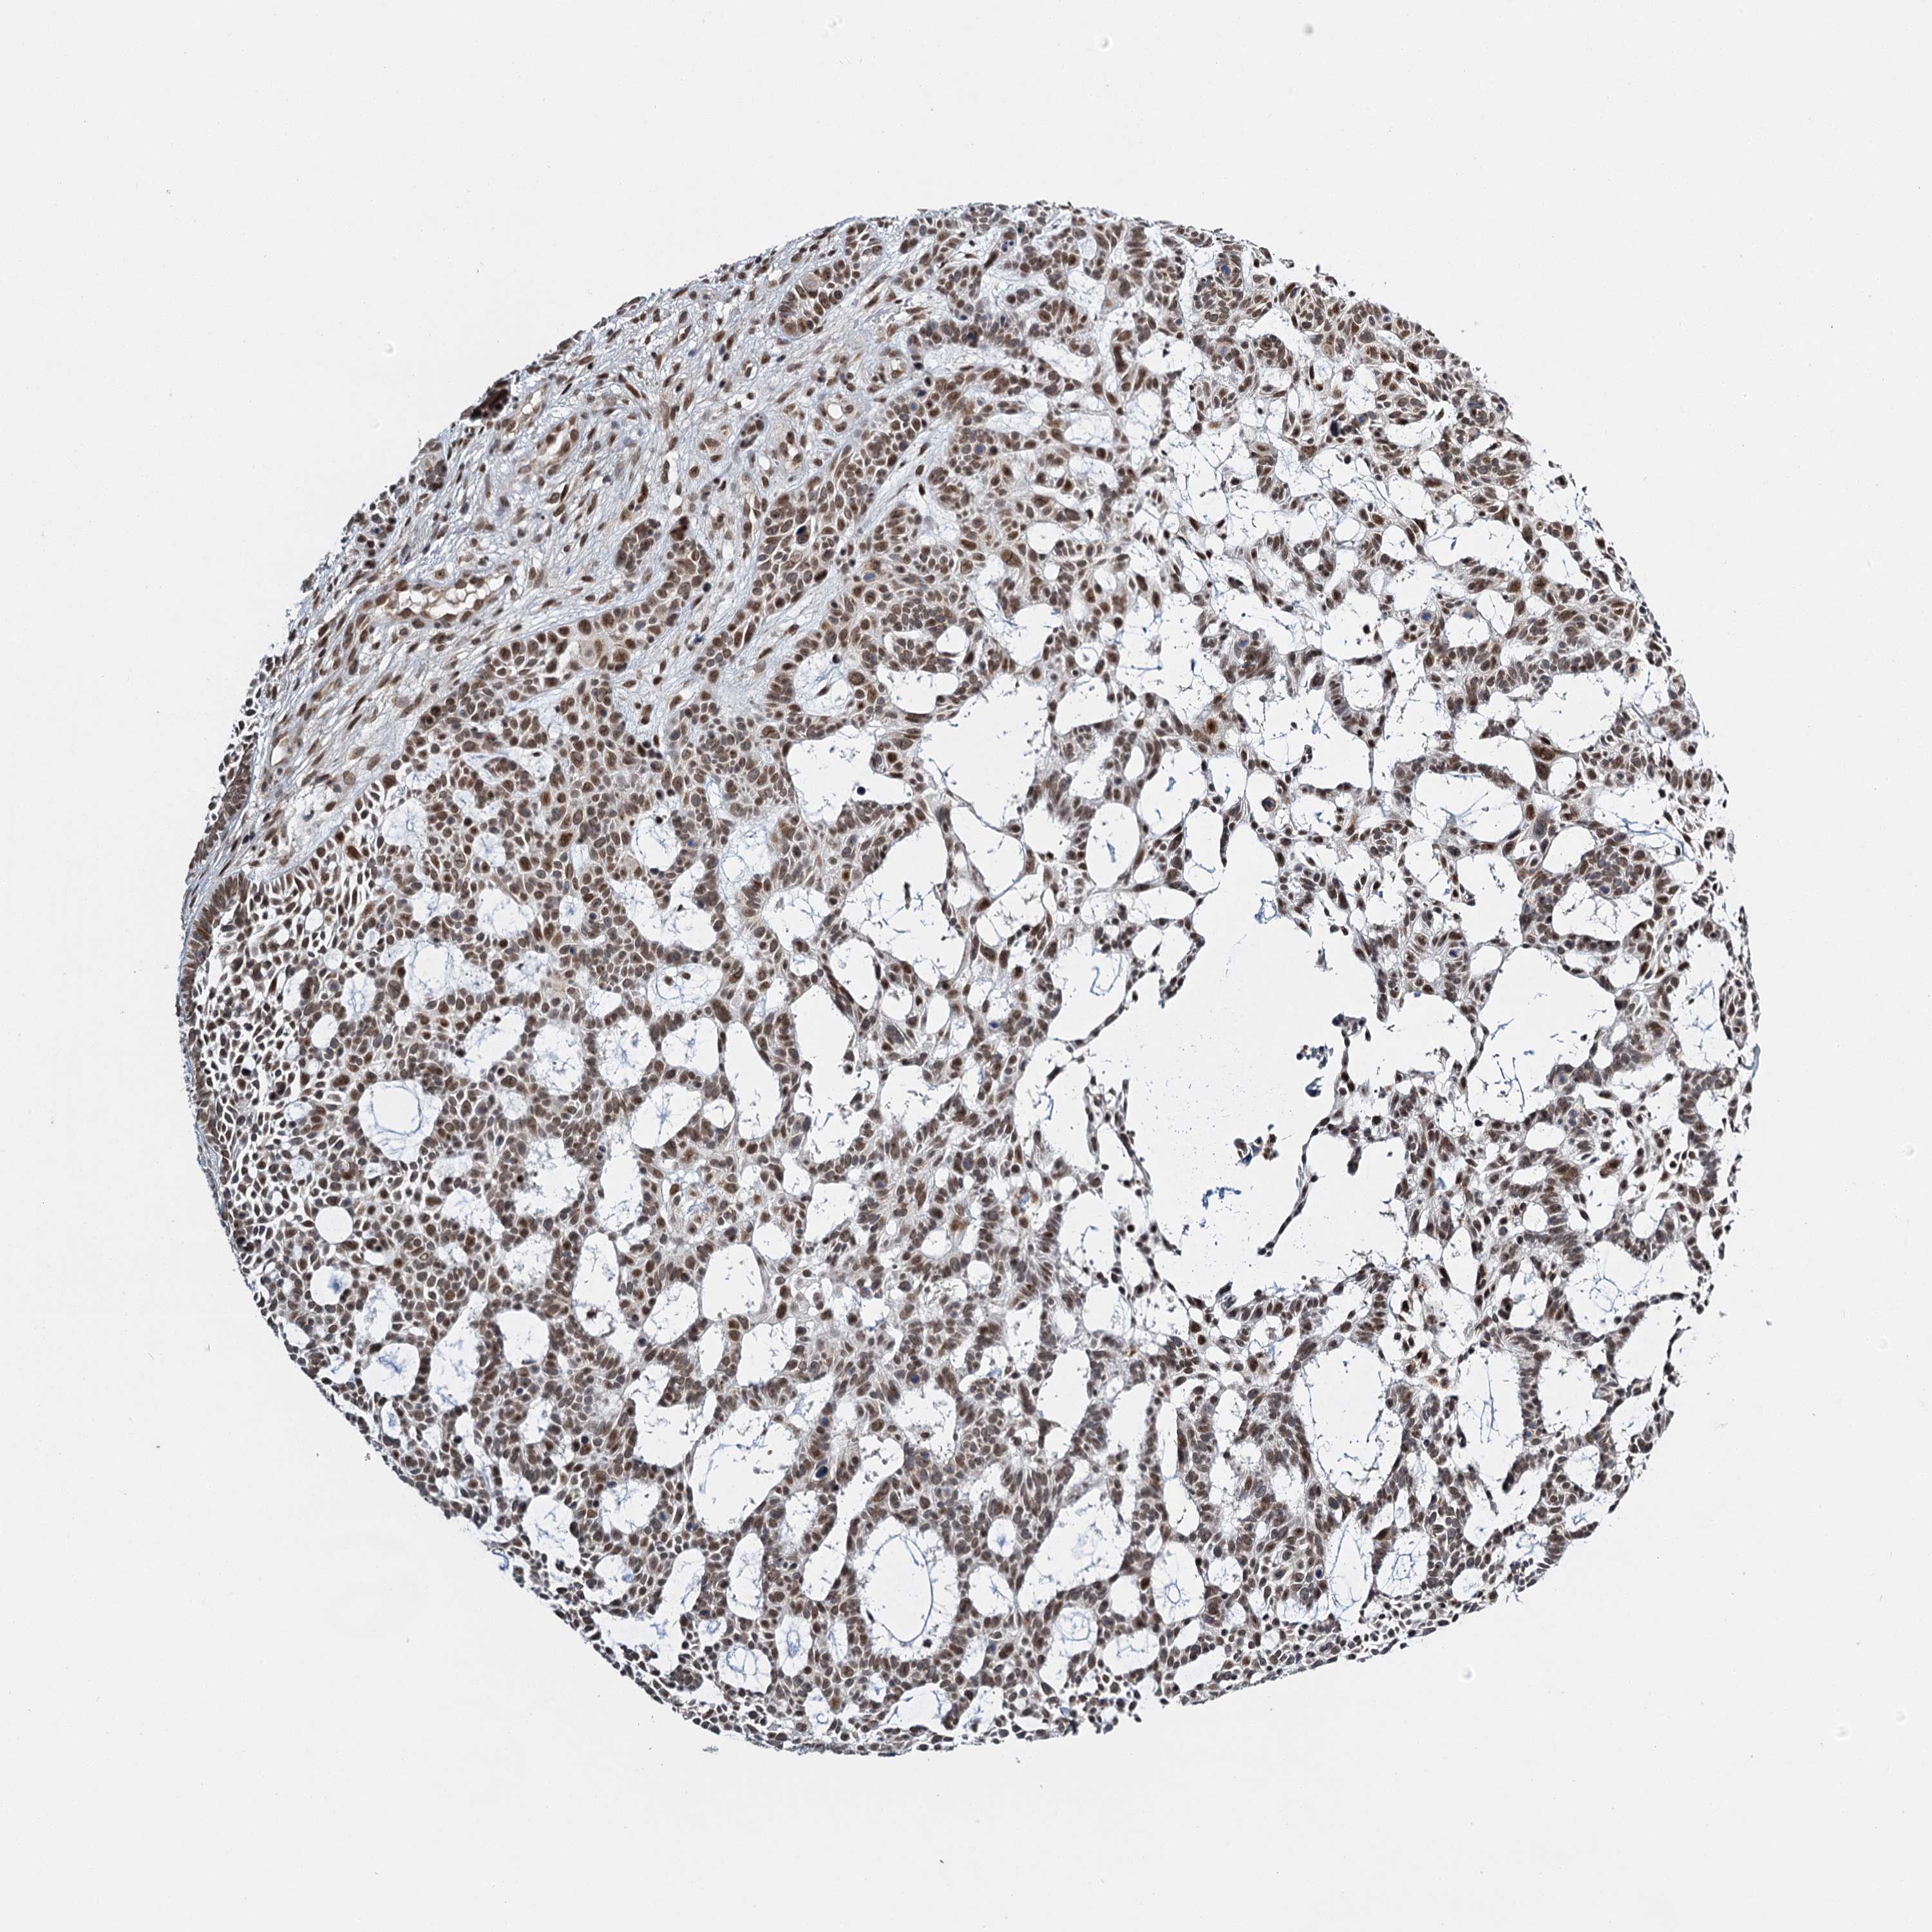

Basal cell and squamous cell cancer

SKIN CANCER - Protein expressioni

A mouse-over function shows sample information and annotation data. Click on an image to view it in a full screen mode. Samples can be filtered based on level of antibody staining by selecting one or several of the following categories: high, medium, low and not detected. The assay and annotation is described here.

Each image is clickable and will lead to virtual microscopy that enables deeper exploration of all samples and also displays staining intensity scores, fraction scores and subcellular localization as well as patient and tissue information for each sample.

Antibody HPA035437

Staining

High

Medium

Low

Not detected

Intensity

Strong

Moderate

Weak

Negative

Quantity

>75%

75%-25%

<25%

None

Location

Nuclear

Cytoplasmic/membranous

Cytoplasmic/membranous,nuclear

Squamous cell carcinoma, NOS

Squamous cell carcinoma, metastatic, NOS